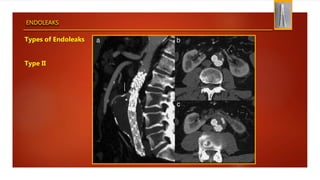

Types of Endoleaks

Type II

ENDOLEAKS